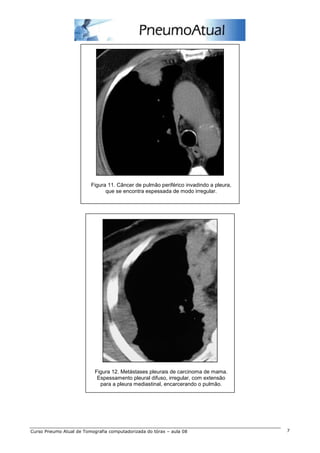

As principais neoplasias pleurais malignas são o mesotelioma e o acometimento pleural secundário por

linfoma e câncer de pulmão. Os sinais na TC de pleura maligna são derrame com realce pleural,

associado a espessamento circunferencial e nodular da pleura, geralmente superior a 1 cm e com

extensão para a pleura mediastinal, com tendência a encarceramento pulmonar (figuras 11, 12 e 13).

Figura 11. Câncer de pulmão periférico invadindo a pleura,

que se encontra espessada de modo irregular.

Figura 12. Metástases pleurais de carcinoma de mama.

Espessamento pleural difuso, irregular, com extensão

para a pleura mediastinal, encarcerando o pulmão.